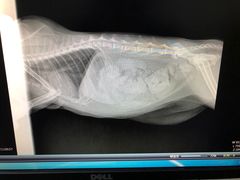

• 乐嘟嘟宠物医院

• -乐嘟嘟宠物医院

桔*桔 | 18-04-22